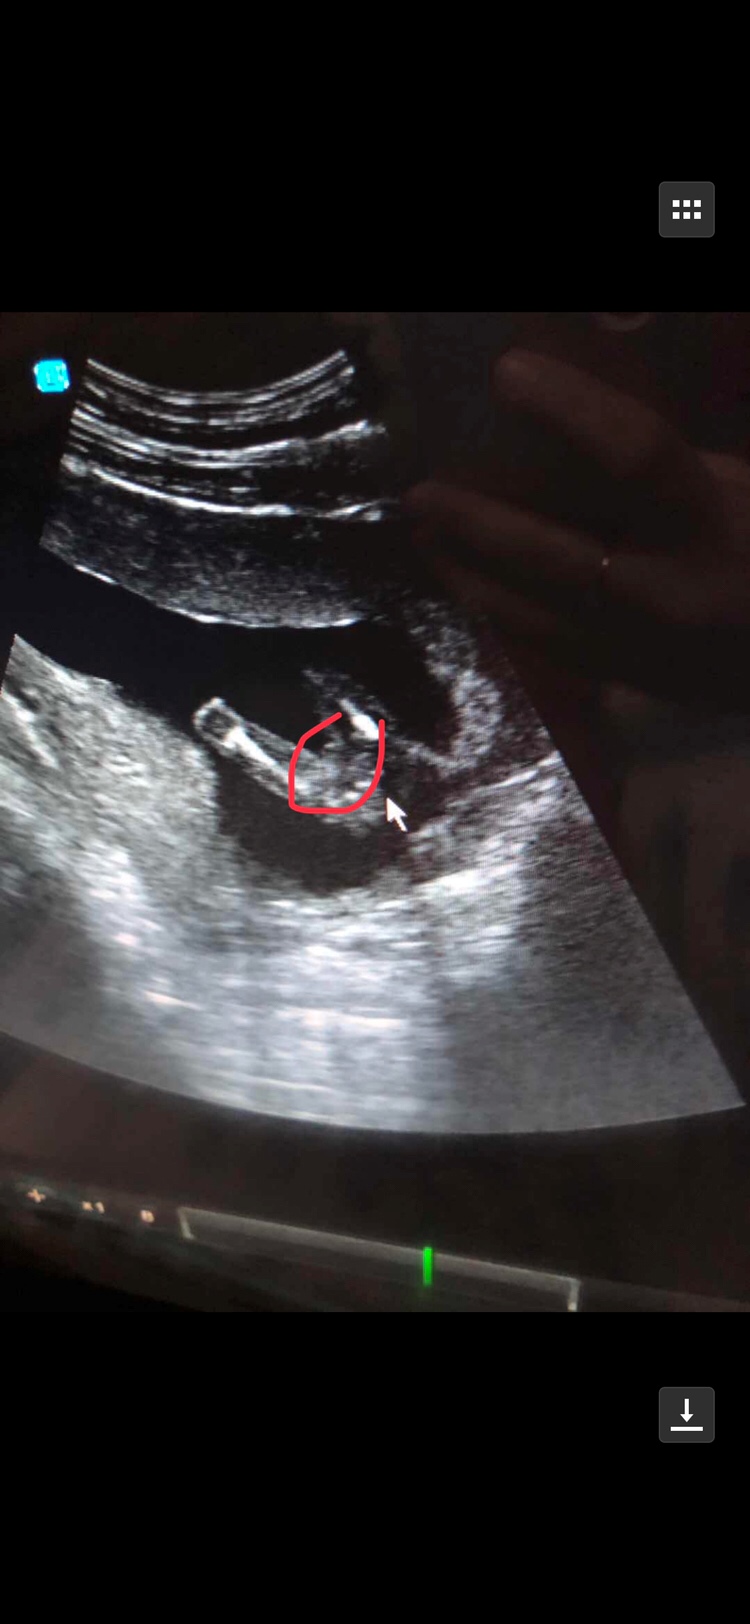

图片上有什么?表情看不懂

看着不像男孩儿,但是孕早期看着像女孩儿的话,过段时间有可能会翻盘的,因为有些胎儿发育的慢,后面长出来就看得清了。如果孕早期看出来是男孩,那基本是没有翻盘的可能的,因为男宝女宝在孕早期长的差不多,长着长着,男宝邪恶特征就明显了。

这个就是女孩的特征,我4个月也是去外面查的,医生男宝的说看的很清楚,说女宝的比较难看清楚

你看的懂那是什么?